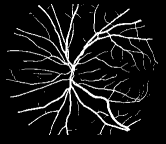

As pointed out in recent works [15, 17], a good semantic segmentation network should learn multi-level features. Further, it should have multiple stages with different receptive fields to learn more inherent features from different scales. FCN, taken as an example, uses skip connections to fuse multiple stages outputs, as well as the HED network, in which a series of side-output layers are added after each stage in VGGNet. The HED network was first proposed for edge detection, and further used for image-level vessel segmentation in recent studies [6, 16], with significant performance. However, our experimental results show that such network architecture is not appropriate for vessel segmentation directly. Figure 1 provides such an illustration. Reasons for this phenomenon are straightforward. On one hand, the side-output of the first layer often contains too many noises. On the other hand, the features produced by the last side-output layer are too coarse due to information loss of pooling operation. Obviously, the inaccurate vessel map of side-output1 and side-output4 should have negative impacts on the final segmentation result.

2.2 Bottom-top short connections

With the deepening of DSN network, the receptive field of each side-output layer gets larger, which makes the corresponding vessel map much blurrier as observed from the first row in Figure 1, especially for side-output4. These observations inspired us to pass low level fine semantic information to high levels to alleviate the blurring situation.

Bottom-top short connections aim to refine high-level segmentation results. However, we can observe from the first two rows in Figure 1 that the vessel map generated by the first side-output layer contains too many noises while the map generated by the last side-output could capture the main vessel structure. Therefore, we propose delivering high-level structural information to the first side-output layer to reduce its noises. We implemented this kind of information delivery by a top-bottom short connection from conv4 to feat_conv1, which can been seen in Figure 4. We first convolved the last convolution of conv4 using 1 convolution kernels with size 33. Then the obtained feature map are up-sampled 8 to get feat_4_1. The information (feat_4_1) passed from conv4 are concatenated with feat_conv1 to form feat_conv1_fuse (see Figure 5). At last, one hand hand, we perform a 11 convolution operation on feat_conv1_fuse to get the information (feat_1_2) delivered to feat_conv2. On the other hand, we performed convolution operation with a kernel size of 11 and sigmoid transformation for feat_conv1_fuse sequentially to obtain the segmentation result (side 1). At last, side 1 is compared with the ground truth to get the loss of the first side-output layer.

In addition, we can observe from Figure 1 that the side-output1 and side-output4 of the BTS-DSN were more accurate compared with those of the DSN.